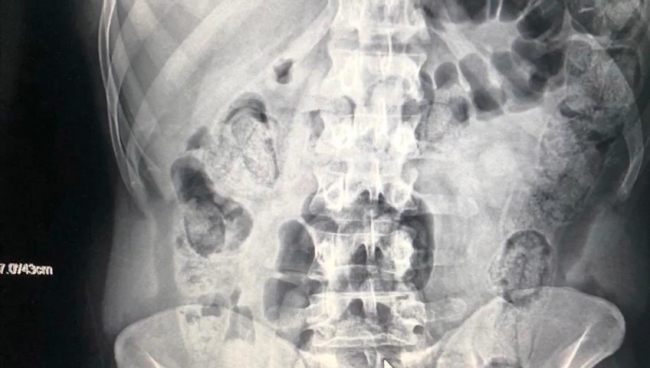

Röntgenleri çekilen ve midelerinde uyuşturucu madde olduğu belirlenen zanlıların vücutlarından tıbbi müdahaleyle 103 fişek halinde 871 gram metamfetamin çıkarılmıştı.